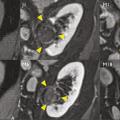

Cryothérapie sous anesthésie locale des tumeurs rénales

Publié le 20 Janvier 2018 || La Revue du Praticien || 68(1):45-7

L’incidence du cancer du rein localisé et de petite taille est en permanente augmentation depuis plusieurs décennies. Cela s’explique en partie par l’essor de l’imagerie médicale puisque plus des deux tiers des cancers du rein sont découverts fortuitement au cours d’un examen d’ima- gerie réalisé pour une autre raison.1, 2 Le…